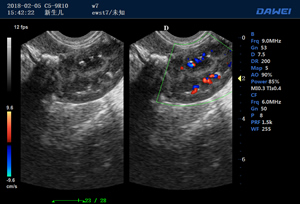

·支持B、C、PW、CW、寬景成像

適用于各種動物的臨床腹部、胸腔,心臟、肌腱、小器官、眼球、生殖系統等的檢查